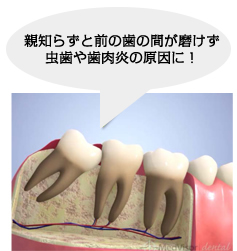

2. 斜めで前の歯にひっかかっている

隣の歯が虫歯になりやすくなります!

このような生え方の親知らずは前の歯に当たっていて、これ以上生えてくる事はありません!

放置しておくと、前の歯が根元付近で虫歯になり神経をとらないといけなくなったり、最悪抜歯になる事もあります!